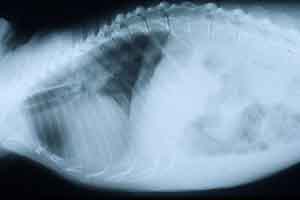

- Case 20-4. Lateral and Dorsal Radiographs. The lateral

view shows diffuse fluid density of the lung space (pulmonary

edema). Both views demonstrate an enlarged cardiac silhouette.

- History: This animal arrived at our facility in 1988.

It underwent an ovariohysterectomy in 1993, and had subsequently

been treated for periodontal disease. In June 1997, it was observed

to have ascites when sedated for a routine health check. Abdominocentesis

was performed and the fluid revealed to be a transudate. A CBC

was normal and serum biochemistry profile revealed a mild increase

of BUN and creatinine. Approximately 1 week later, the animal

was noted to be weak and anorexic. It was again sedated and intravenous

fluids were administered. On auscultation, this monkey was noted

to have a gallop rhythm. Thoracic radiographs revealed an enlarged

cardiac silhouette, compatible with generalized cardiomegaly.

An ECG revealed increased P wave amplitude compatible with right

atrial enlargement, and increased PR interval consistent with

1st degree heart block. A repeat serum biochemistry profile indicated

a moderate increase of BUN, creatinine, and bilirubin. Several

days later, this animal was noted to be increasingly weak and

anorexic, and was euthanatized.